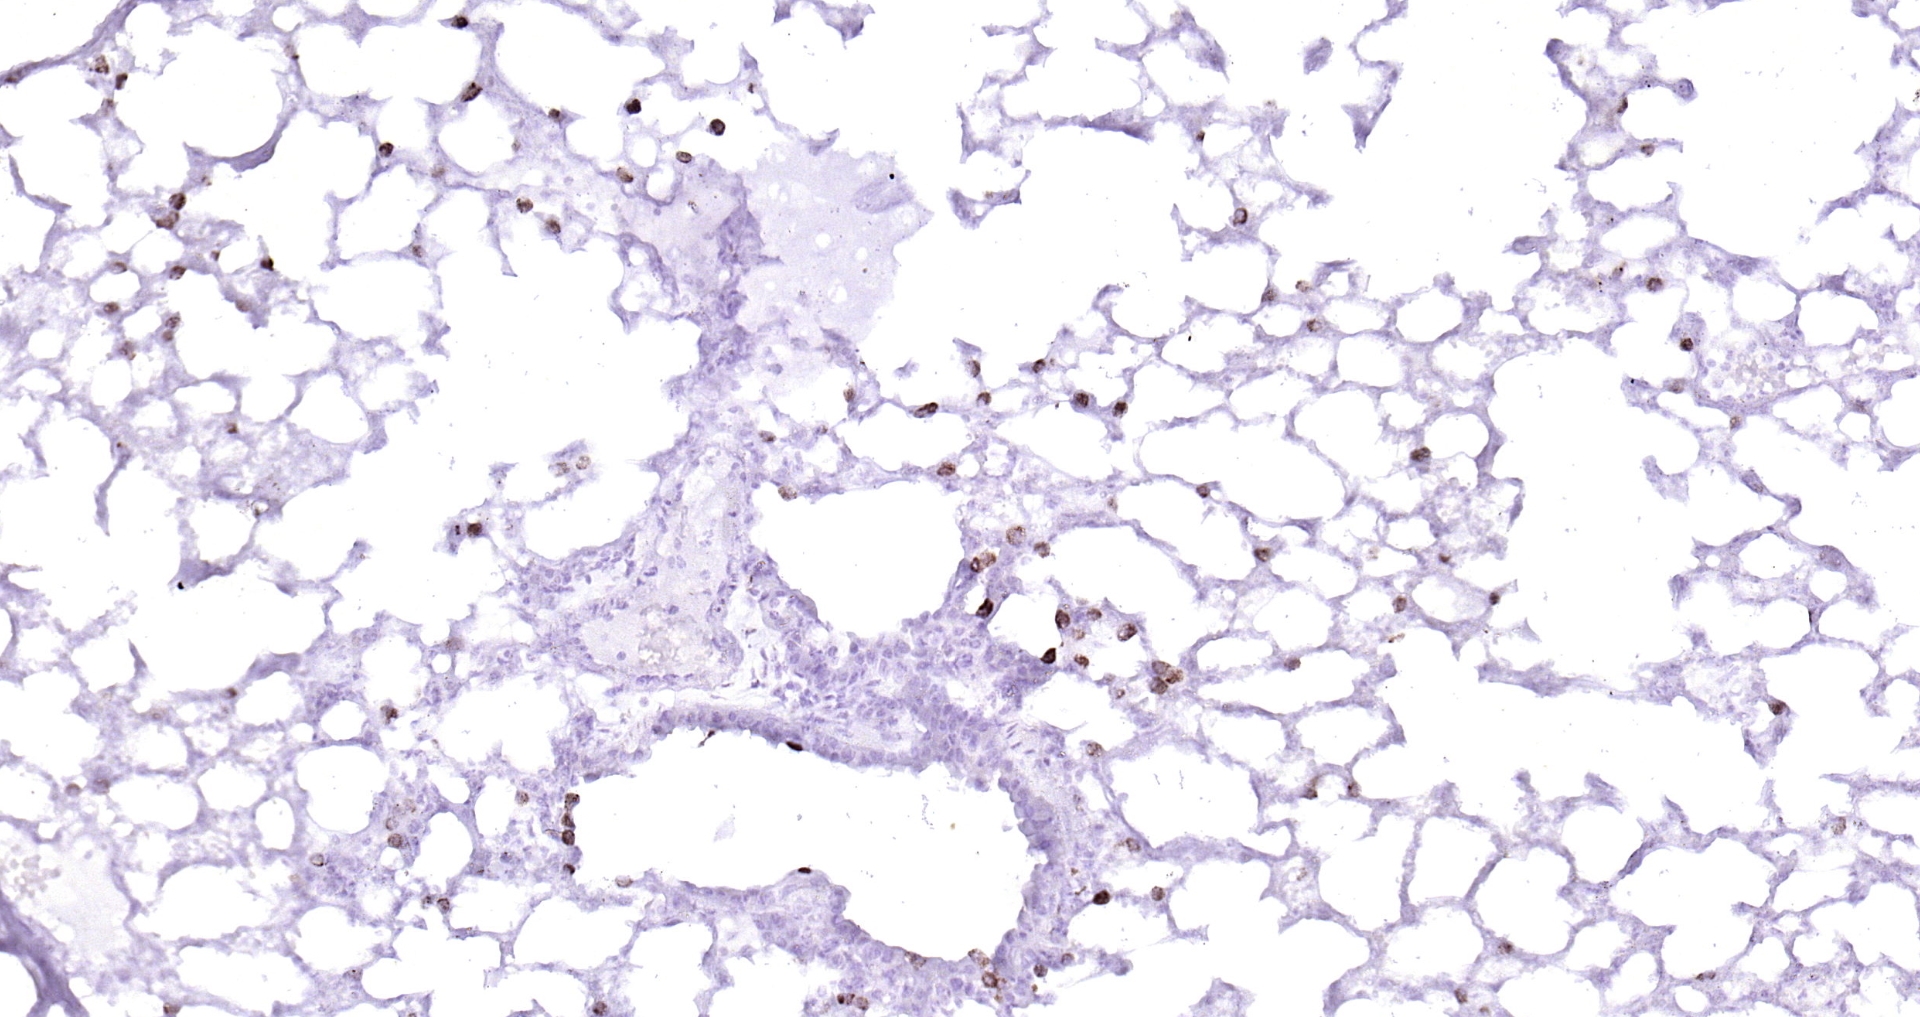

CD68 Polyclonal Antibody

Applications ELISA, IHC-P, IF(IHC-P), IF(IHC-F), IF(ICC)

IHC-P 1:200-400